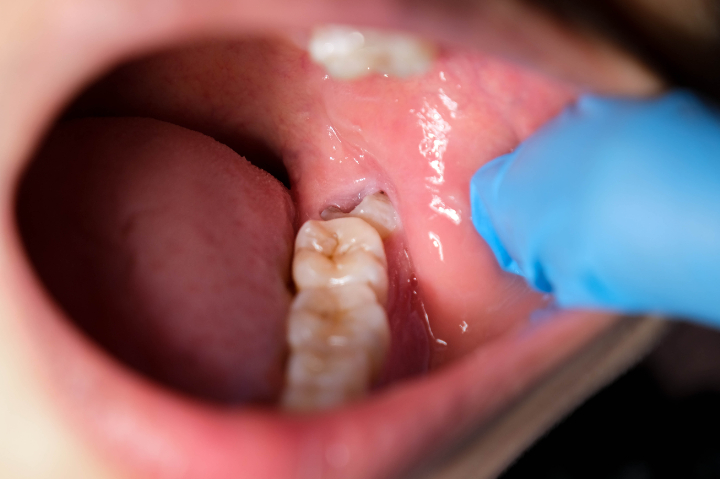

親知らずの周囲に炎症が生じる状態を、智歯周囲炎といいます。親知らずが半分だけ生えていたり、歯ぐきの中に埋まっていたりすることで、細菌や汚れが溜まりやすくなって発生します。

一度炎症を起こすと、歯みがきでは完全に清掃できないため、体調の変化やストレスなどをきっかけに化膿や腫れを繰り返すことがあります。また、炎症が隣の歯にまで及ぶと、健康だった歯が虫歯や歯周病になるリスクも高まります。

智歯周囲炎を繰り返す場合、親知らずの抜歯が根本的な対策として推奨されます。

特に、斜めや横向きに生えていたり、歯ぐきに半分埋もれている状態では、隣の歯との間に汚れがたまりやすくなります。この部分は見えにくく、歯ブラシの毛先も届きにくいため、気づかないうちに虫歯になったり、歯ぐきに炎症が起こることがあります。